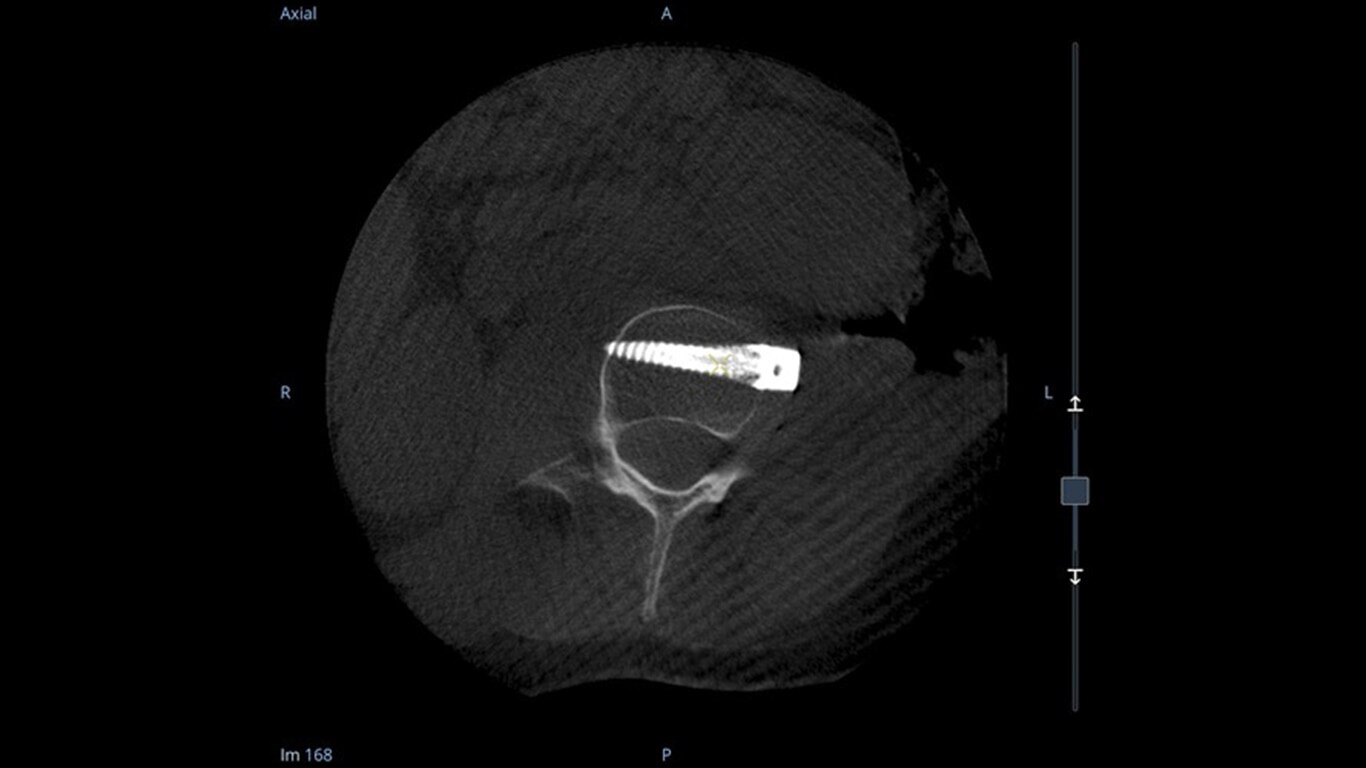

19 cm3 CT-like images presented intraoperatively in minutes

See more levels during a spinal fusion, or more of the pelvis or femur during an orthopedic procedure. With a 19 cm x 19 cm x 19 cm volume, OEC 3D captures a 67% greater volume than other 3D C-arms*.

Enhance intraoperative decision-making with visualization capabilities of Augmented Fluoroscopy in the OEC 3D Volume Viewer. Analyze five perspectives with 3D imaging tools including Multi-Oblique Mode, scrolling 512 slices, zoom, and more.